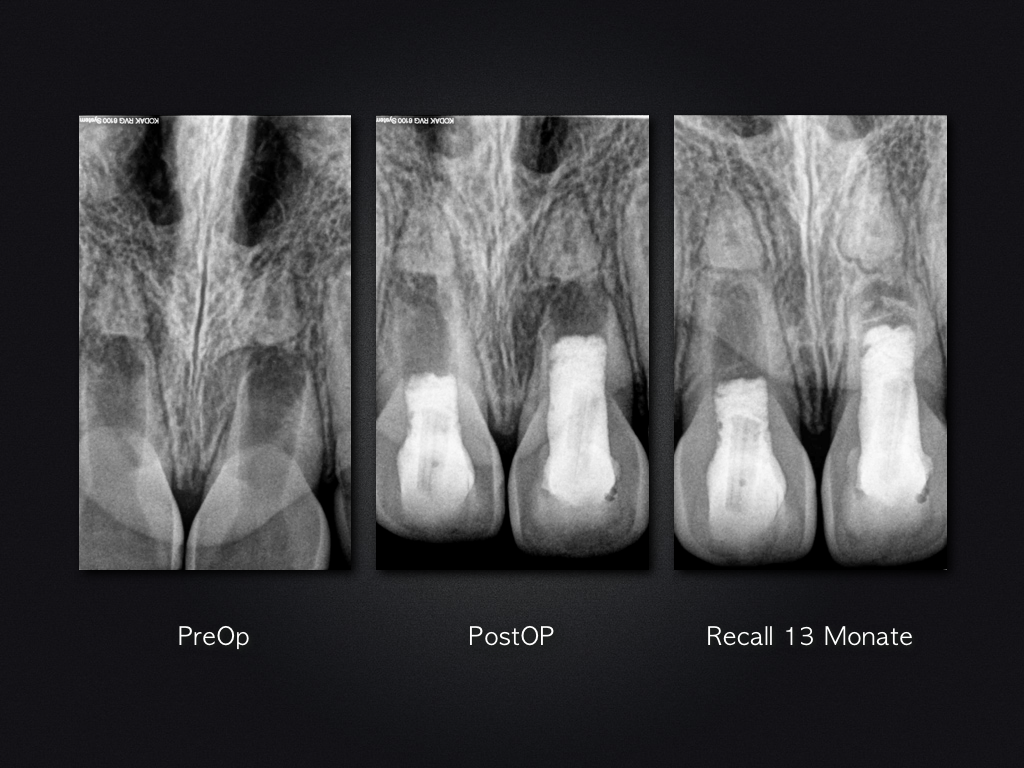

Letzte Ausfahrt Regeneration – Recall